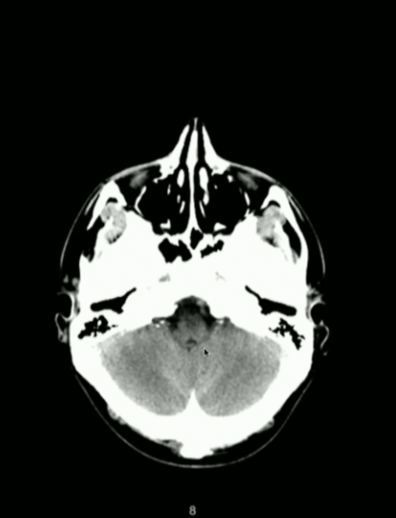

<p>What Part of Brain Stem?</p>

What Part of Brain Stem?

• Pons

• Look for Basilar Groove